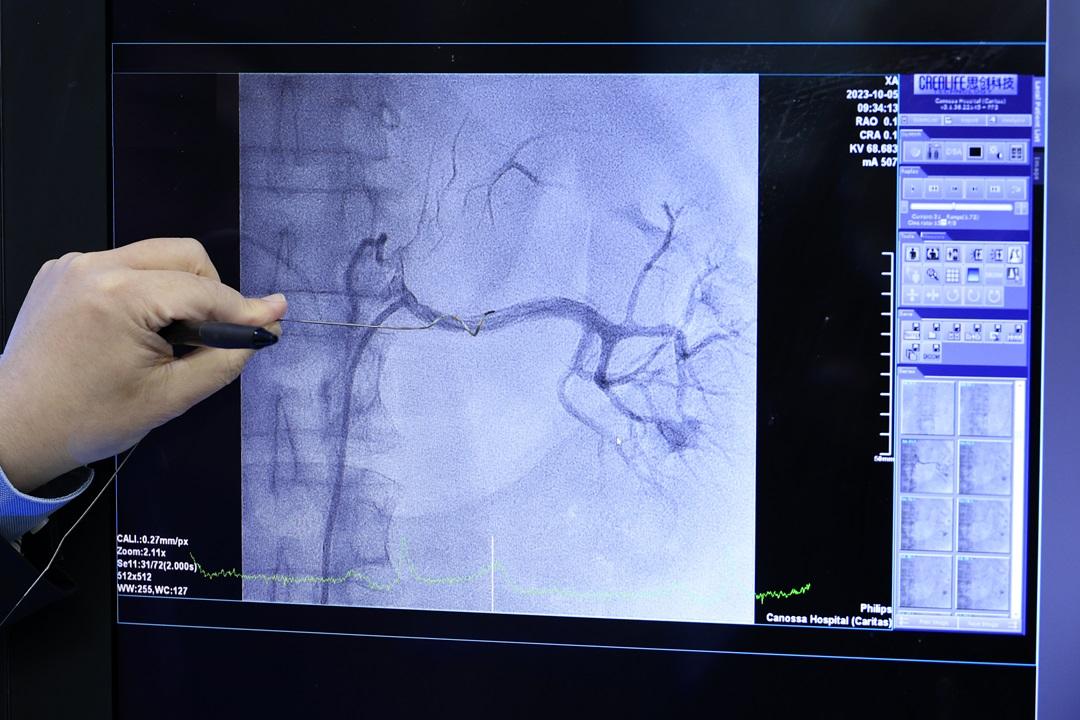

林逸賢醫生指腎臟交感神經消融術是利用導管及高頻率電波進行治療,以減低腎動脈神經的活躍程度,降低腎素分泌以控制血壓。

腎臟交感神經消融術是一種介入治療,醫生會於病人大腿內側進行局部麻醉,並從其中一側大腿的股動脈以打針方式置入一條中空鞘管,以便將治療專用的導管放入體內。當導管到達其中一邊腎臟動脈後,會在4個合適的位置同時利用高頻率電波進行神經組織電擊治療,每次需時約1分鐘,當一邊的腎動脈完成治療後,醫生便會於另一邊腎重複步驟,直至手術完成,便會取出所有治療的導管器材。手術可以減低腎動脈附近神經線的活躍程度,降低腎素(血管收縮素)分泌以達控制血壓的目的。